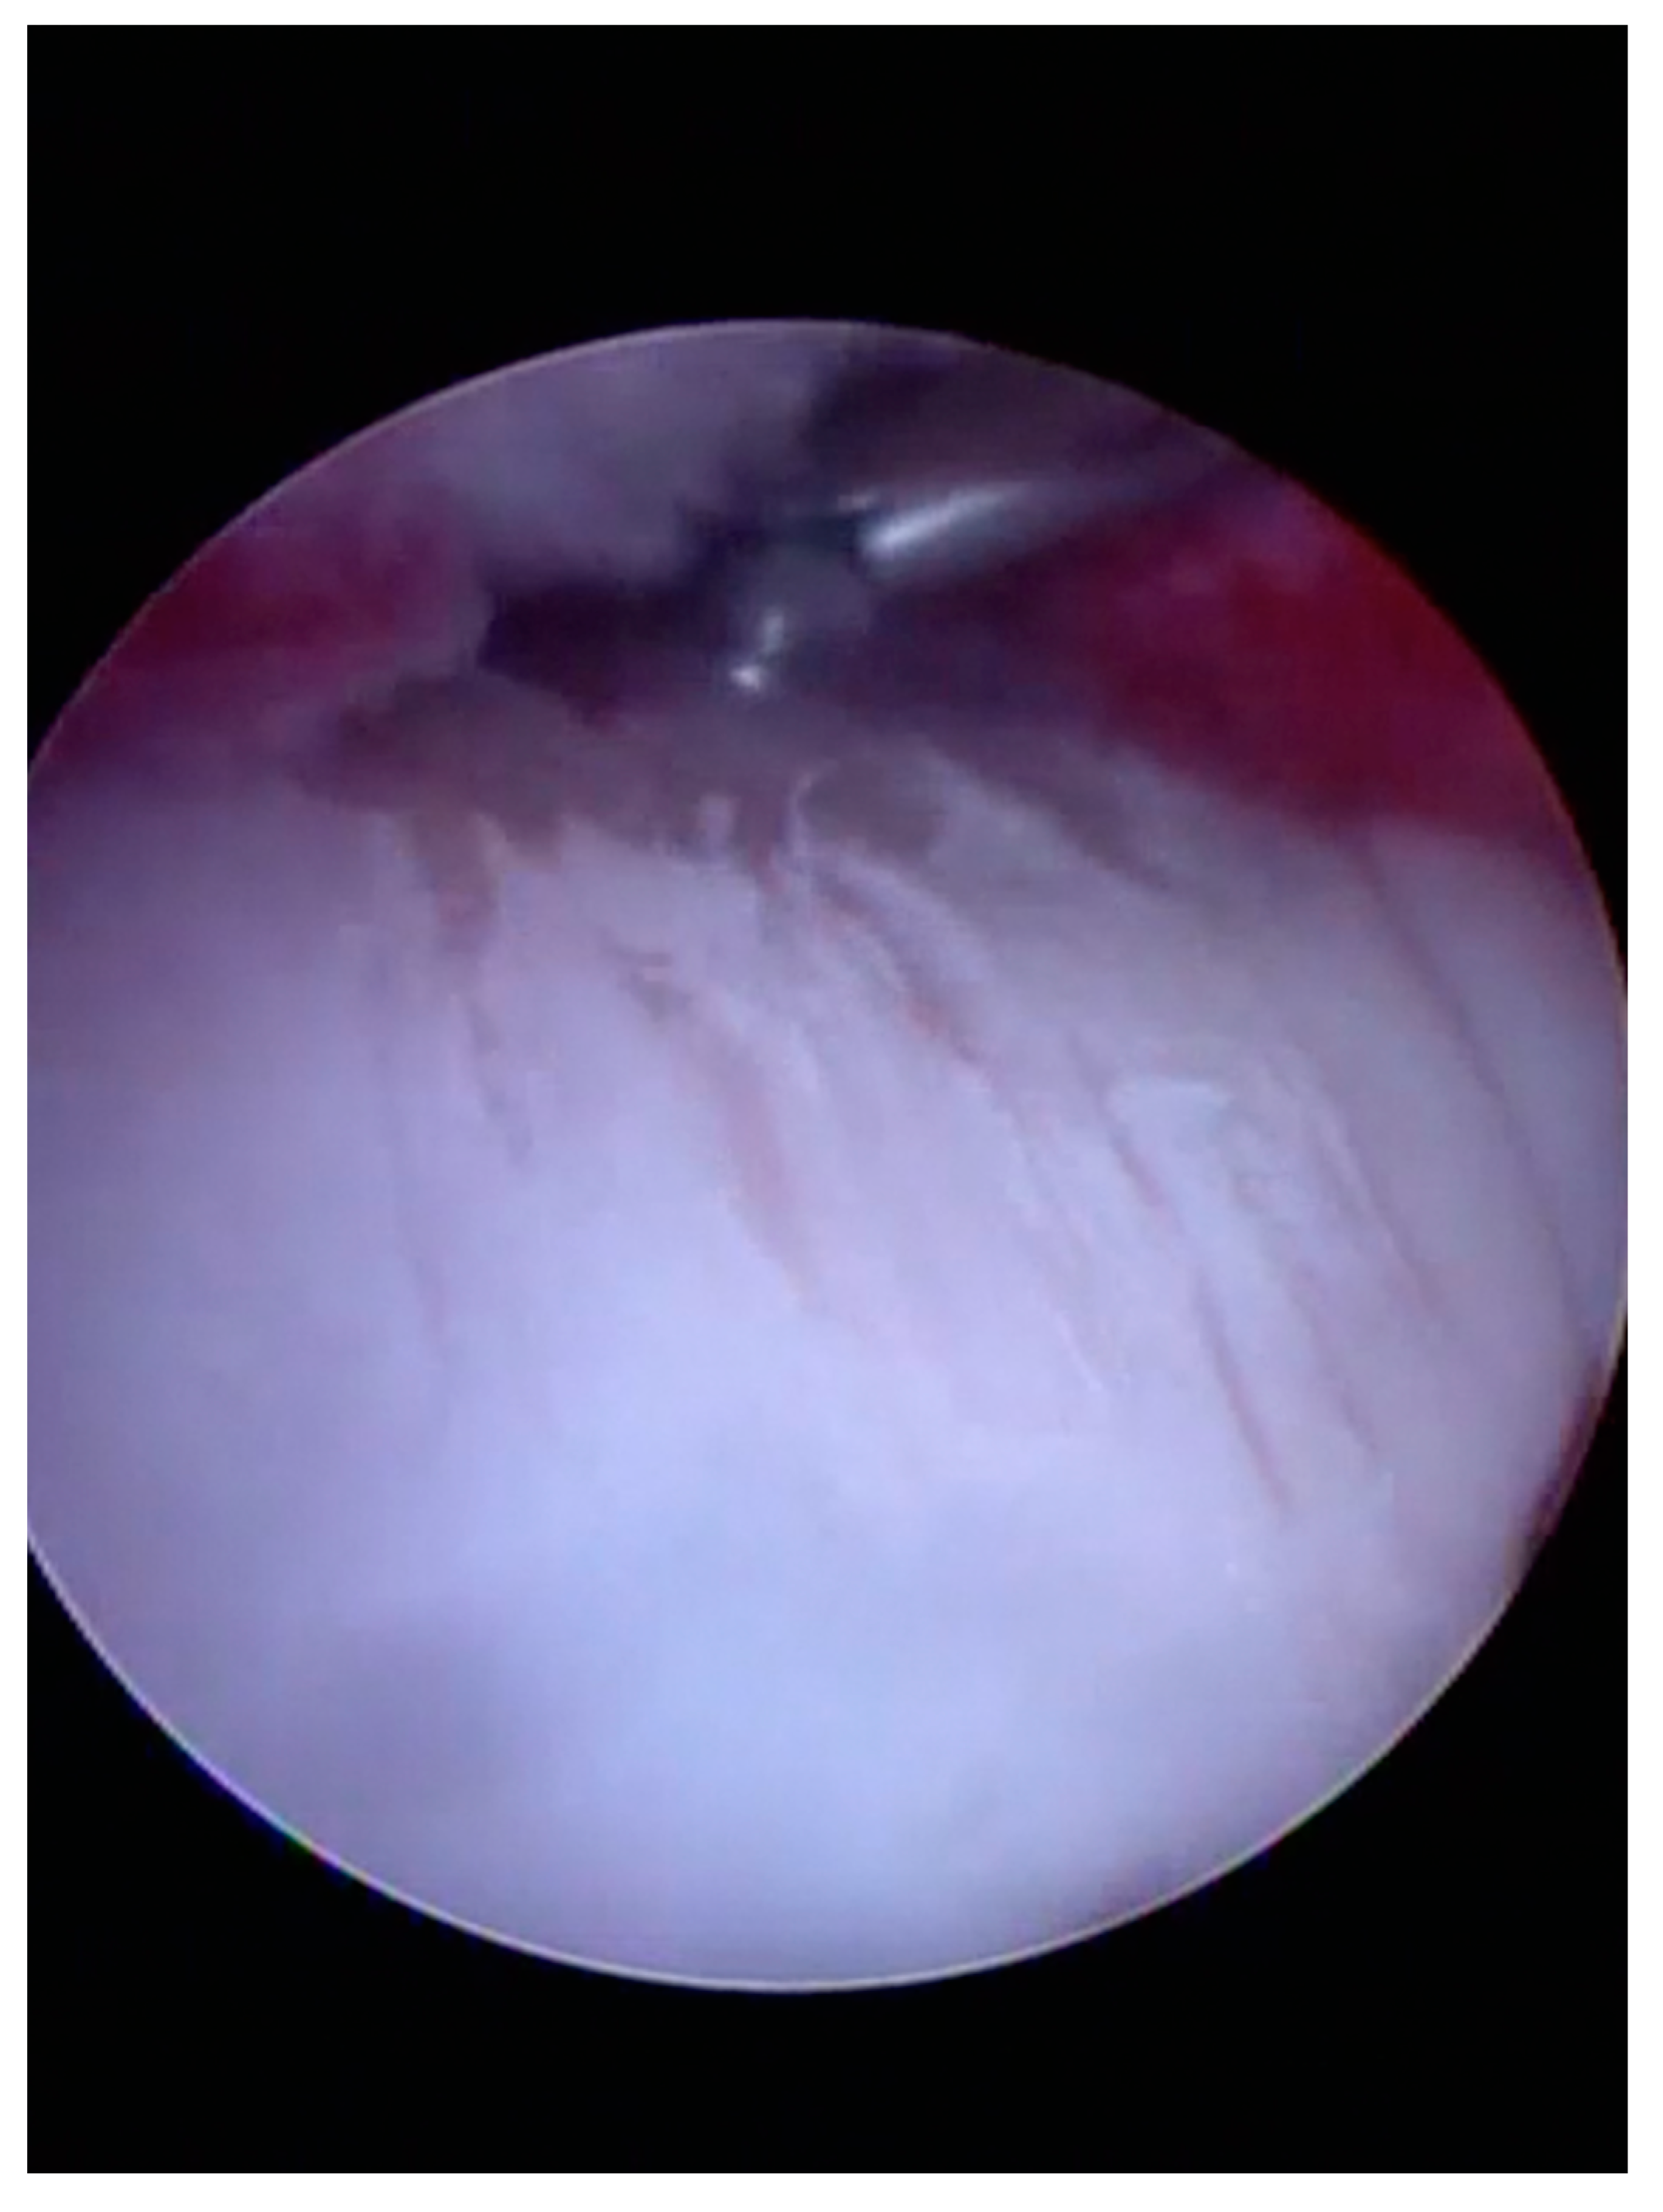

- Proliferation (hyperplasia and hypertrophy) and hyperemia of the synovial membrane (Figure 14)

- Articular surface fibrillation (Figure 4)